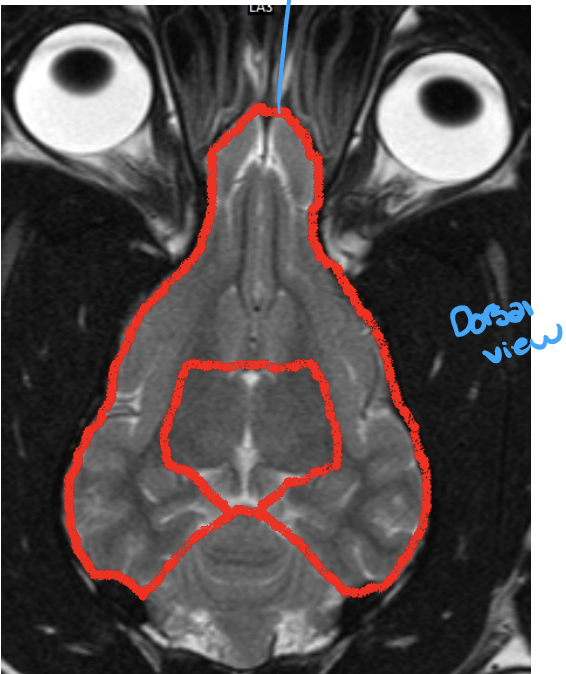

what structure is shown here

telencephalon

2 cerebral hemispheres